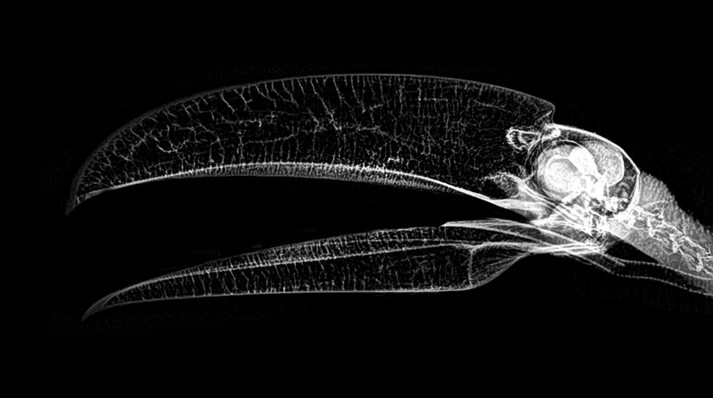

Зоопарк города Портленд (Орегон, США) решил порадовать любителей животных необычной «фотосессией» по случаю Хеллоуина – на своем сайте он опубликовал рентгеновские снимки своих постояльцев.

В подборку попали еж, хамелеон, фламинго, амурский тигр, летучая мышь, черепаха и многие другие.

На самом деле эксперимент был сделан не только для красоты. Цифровая рентгенография позволяет работникам ветеринарной медицины получать рентгеновские результаты быстрее и точнее настраивать изображение после их получения, а следовательно - минимизировать анестезию и время осмотра животных.

Каждое животное в зоопарке штата Орегон проходит обычный медицинский осмотр и часто эти проверки включают и рентгеновские фото.